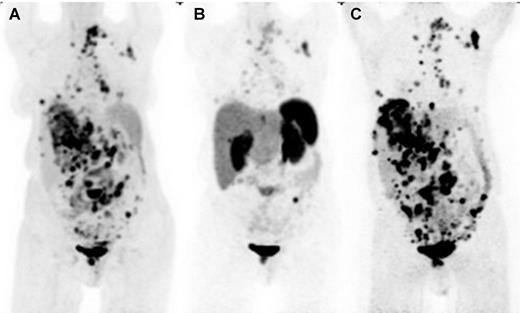

Selection of HSA- 131 I-MIBG over PRRT for metastatic paraganglioma based on superior norepinephrine transporter expression imaged by 124 I-MIBG PET/CT and compared with 18 F-FDG PET/CT. The anterior maximum intensity projection images of 18 F-FDG PET-CT(A), SSTRI by 68 Ga-DOTATATE PET/CT (B), and norepinephrine transporter imaging by 124 I-MIBG PET/CT (C) in a case of widely metastatic paraganglioma. 124 I-MIBG demonstrates more disease sites than 18 F-FDG, as well as has significantly more intense and numerous lesion uptake than 68 Ga-DOTATATE, making MIBG therapy the preferred option for treatment in this case. Advantages of comparing PET ( 68 Ga-DOTATATE) with PET ( 124 I-MIBG) and ability to do prospective dosimetry are potential advantages of 124 I-MIBG over 123 I-MIBG, although this technique is not widely available.